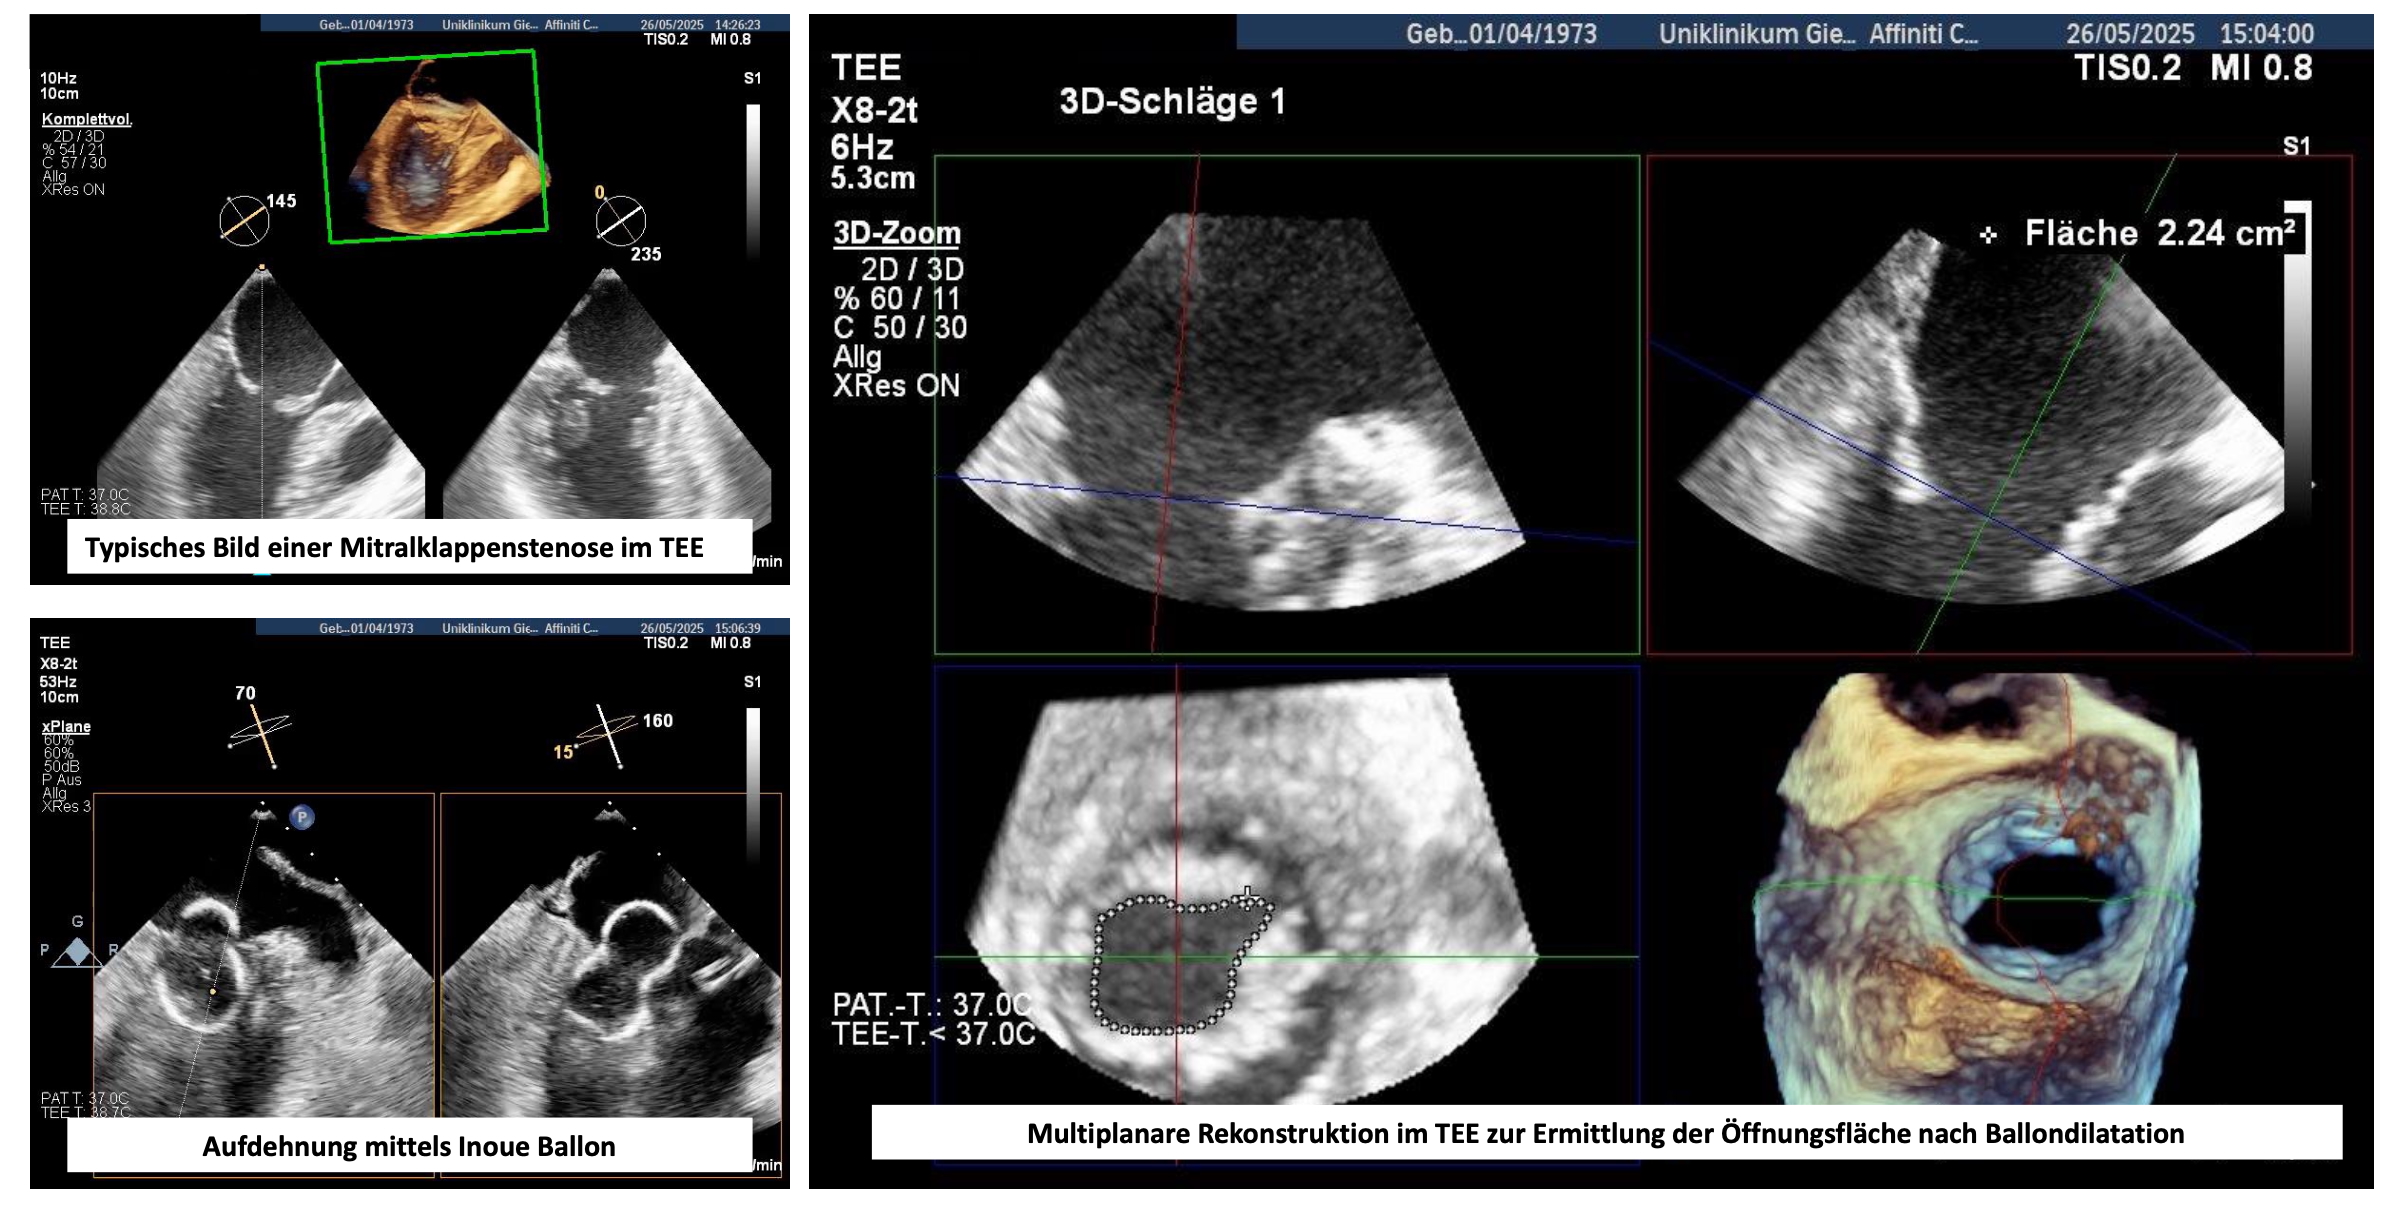

Die Ballonvalvuloplastie (perkutane Mitralkommissurotomie) ist ein minimalinvasives Verfahren zur Behandlung der Mitralklappenstenose, vor allem bei rheumatischer Genese. Sie kommt bei symptomatischen Patienten mit reduzierter Klappenöffnungsfläche (<1,5 cm²) und günstiger Klappenmorphologie (Wilkins-Score ≤8) zum Einsatz. Wichtige Ausschlusskriterien sind eine relevante Mitralklappeninsuffizienz oder ein Thrombus im linken Vorhof.

Über die Vena femoralis wird ein Ballonkatheter eingeführt. Nach einer transseptalen Punktion wird der Ballon durch die Mitralklappe geführt und aufgeblasen, um die verklebten Kommissuren zu lösen. Die Prozedur verbessert die Klappenöffnung, senkt den Druckgradienten und lindert Symptome. Die Erfolgsrate ist hoch, die Komplikationsrate niedrig.

Damit stellt die Ballonvalvuloplastie ist eine effektive, katheterbasierte Alternative zur Operation – besonders bei jungen Patienten mit geeigneter Anatomie.

Schuckultraschallbilder während der interventionellen Behandlung einer relevanten Mitralklappenstenose